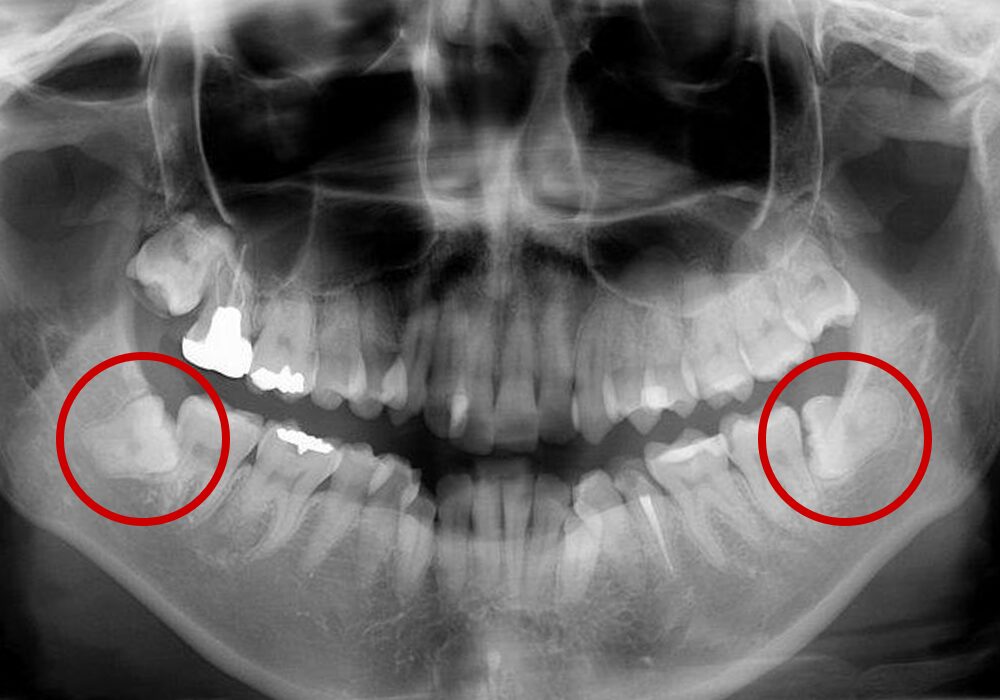

親知らずとは大臼歯(大人の奥歯)の中で一番後ろに位置する第3大臼歯です。

智歯とも呼ばれ20歳前後で生えてくることが多く、一般的には上顎の左右2本と下顎の左右2本、計4本ありますが、もともと親知らずのない人や4本揃ってない人など個人差があります。

硬い物を噛まずに顎が退化していると言われる現代では、親知らずが生えてくる顎のスペースがなくなることが多く、横や斜めに生えてきたり、歯ぐきが被っていることがあります。

親知らずは、まれに隣の歯を圧迫するような生え方で成長することがあります。